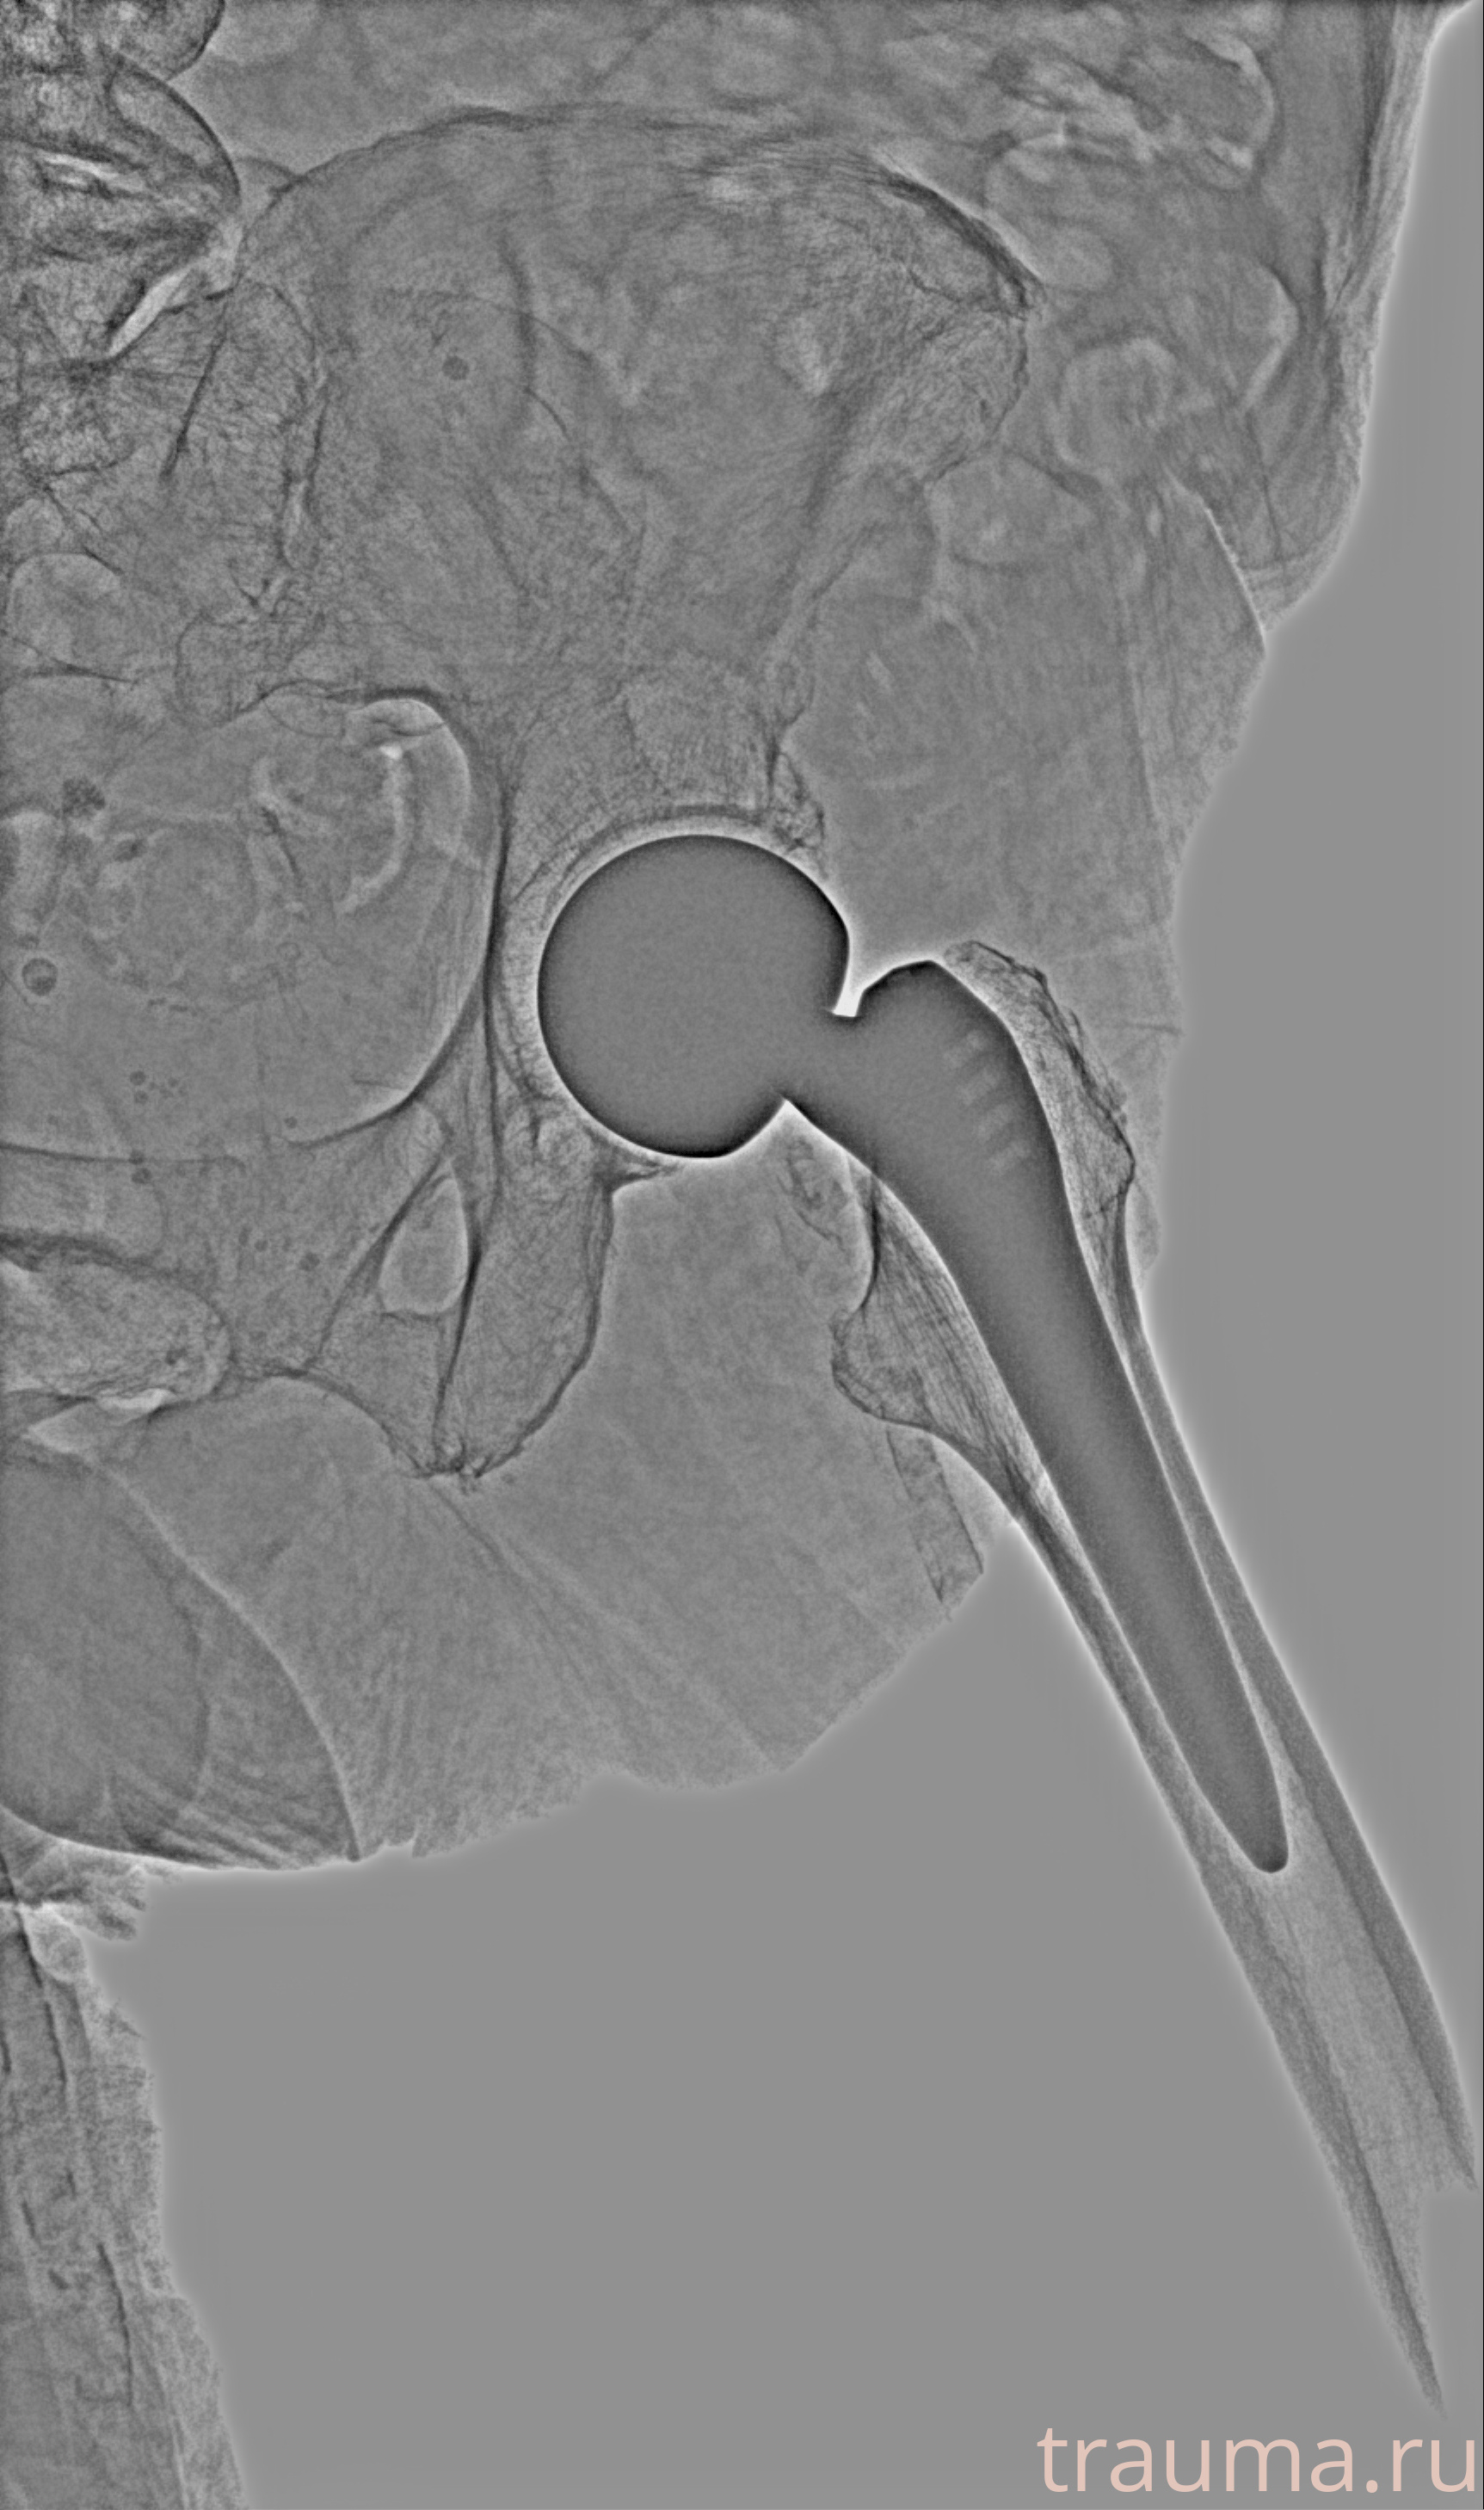

Первая помощь при переломе шейки бедра

Рентген на дому: по вашему адресу приезжает врач-рентгенолог, травматолог-ортопед с мобильным рентгеновским аппаратом, проводит диагностику травмы или заболевания, делает необходимые рентгенограммы, дает рекомендации по дальнейшему лечению. Получить качественные снимки в домашних условиях возможно благодаря уникальной методике, разработанной МосРентген Центром для института  Склифосовского